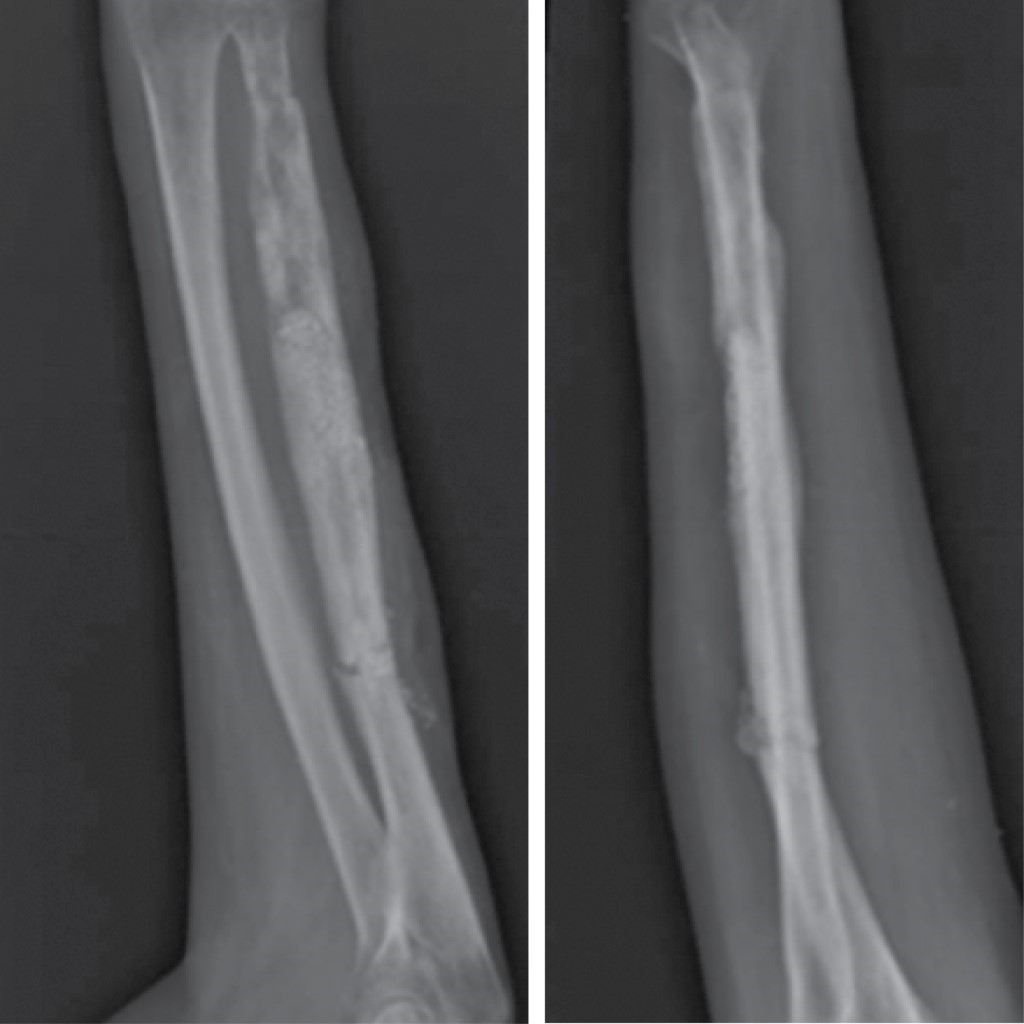

Figure 1

Figure 2

Figure 3

Figure 4

Figure 5

Figure 6

Figure 7

Figure 8